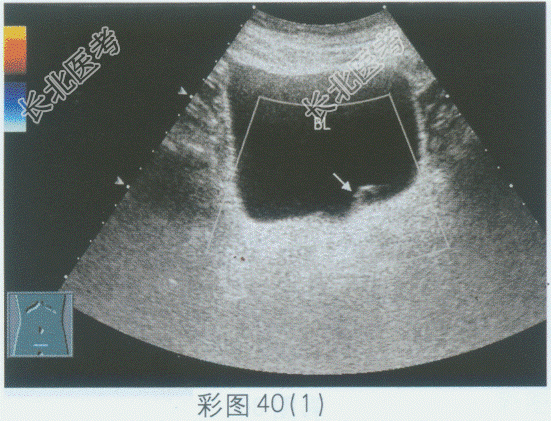

- 单项选择题临床资料:男, 75岁,自述下腹部不适。

超声综合描述: 膀胱三角区左输尿管开口处可见直径1.2cm圆形无回声区,无回声区与左输尿管相通, 动态观察随输尿管蠕动无回声有节律性变化。见彩图40。

超声提示: A、膀胱憩室

B、左输尿管囊肿

C、左输尿管憩室

D、左输尿管脱垂

E、输尿管增生